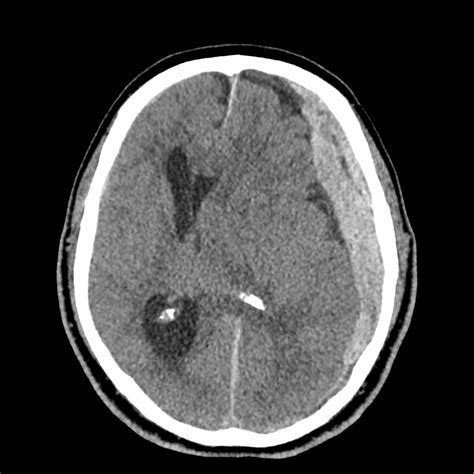

Diagnosis and Imaging

When an uncal herniation brain shift is suspected, time is the absolute priority. Diagnostic imaging is required to confirm the presence and location of the mass effect. A Computed Tomography (CT) scan is the gold standard in an emergency setting because it is fast and widely available. It can reveal:

Finding Clinical Significance

Midline Shift Indicates significant pressure pushing structures across the center of the brain.

Effacement of Basal Cisterns Suggests the brain tissue is being forced into areas where it does not belong.

Temporal Lobe Mass Identifies the primary cause, such as a bleed (hematoma) or tumor.

• uncal herniation on ct scan